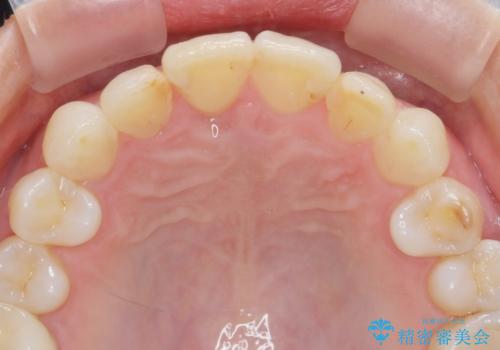

インビザラインで行う前歯のみの部分矯正

- 長年気になっていた前歯の歯並びを改善したいと、矯正治療を希望され思い切って来院されました。

費用と期間を相談し、「気になっているのは前歯だけ。」とのことでしたので前歯のがたつきのみをインビザラインで改善する矯正治療の計画を立てます。

しっかりとマウスピースの装用時間を守っていただき、非常にスムーズに治療を終了することができました。